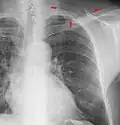

A chest X-ray showing a very prominent wedge-shape area of airspace consolidation in the right lung characteristic of acute bacterial lobar pneumonia.